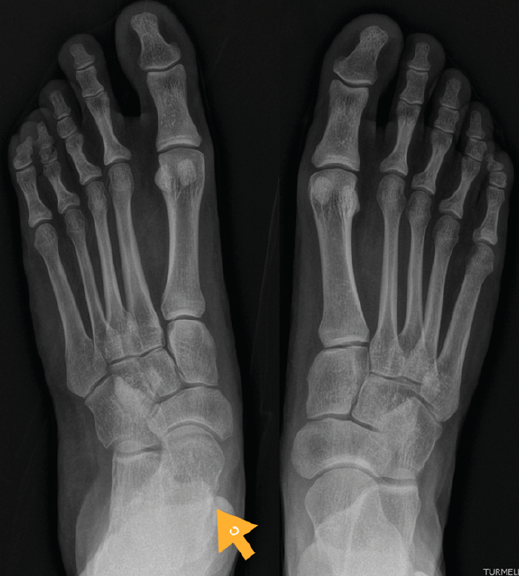

Figura 7. Radiografía del segundo caso: sinostosis talocalcánea media en ambos pies.

Se trata de una paciente mujer de 18 años de edad, higienista dental, sin antecedentes patológicos de interés, que presenta pies planos valgos bilaterales dolorosos, el derecho de 23° y el izquierdo de 21° de valgo, por sinostosis calcaneoastragalina media en ambos pies. En ella observamos básicamente una clínica de dolor en el seno del tarso, con déficit de movilidad de la articulación subtalar en ambos pies. Se realiza estudio mediante radiografías de los pies y los tobillos en carga y TAC de ambos pies (afectación bilateral). Radiológicamente, las articulaciones tibioperoneoastragalina y subtalar están preservadas. Se diagnostica de coalición tarsal de tipo 4 de la clasificación de Rozansky(26). El balance articular es de: flexión = 45°; extensión = 20°; inversión = 0°; eversión = 0°. La escala de la AOFAS para el tobillo derecho presentaba una puntuación de 62 (20-37-5). Los ángulos radiológicos iniciales son: Moreau-Costa-Bartani interno = 141°; declinación talar = 18,4°; Meary = 6,3°; Kite = 25,6°; taloescafoideo = 48,3°.